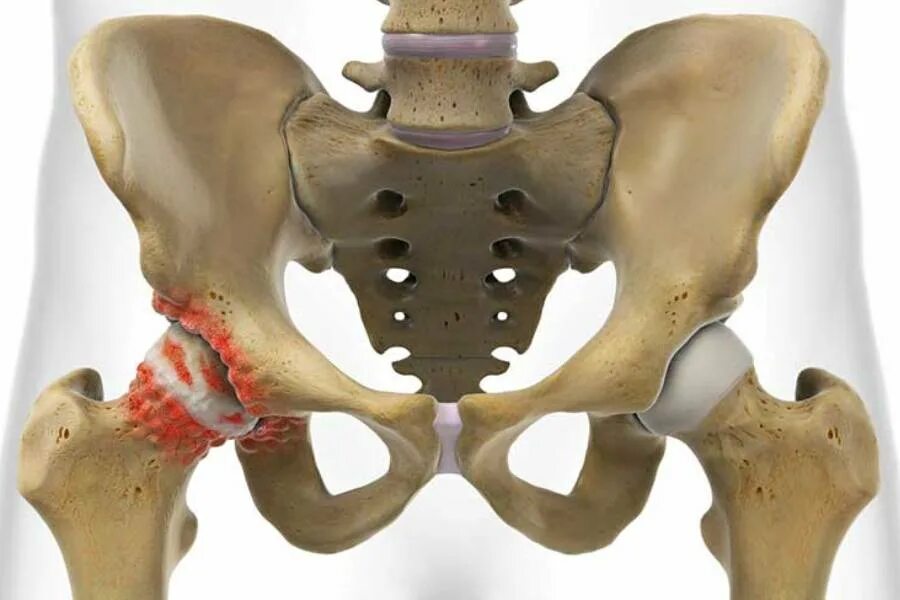

Тазобедренный сустав это